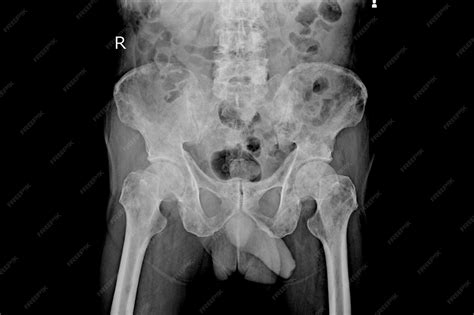

• Ewing Sarcoma: This type of cancer is more common in children and young adults and can occur in any bone but is most frequently found in the pelvis, femur, and ribs.

• Chondrosarcoma: This cancer develops in the cartilage cells and is more common in adults. It often affects the pelvis, shoulders, and ribs.

• Imaging Tests: X-rays, CT scans, MRI scans, and bone scans can help identify bone abnormalities and determine the extent of the cancer.